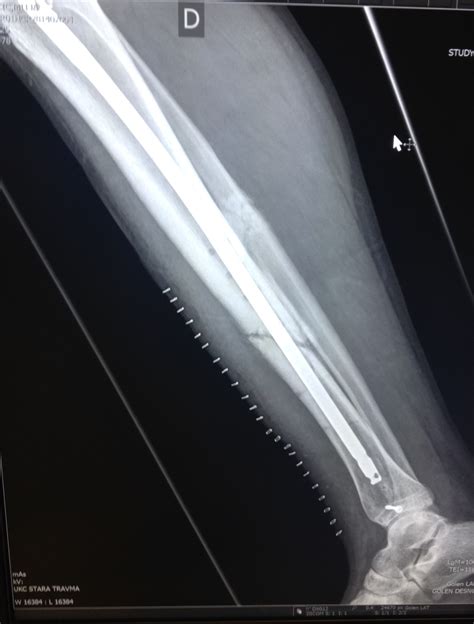

• Imaging Tests: X-rays are the primary imaging tool used to confirm a Tib Fib Fracture. In some cases, additional tests such as CT scans or MRIs may be required for a more detailed view of the fracture.

• Open Reduction and Internal Fixation (ORIF): The bone is realigned and held in place with plates, screws, or rods.

• Intramedullary Nailing: A rod is inserted into the marrow cavity of the bone to stabilize the fracture.

• External Fixation: Pins or screws are inserted into the bone and connected to an external frame to stabilize the fracture.